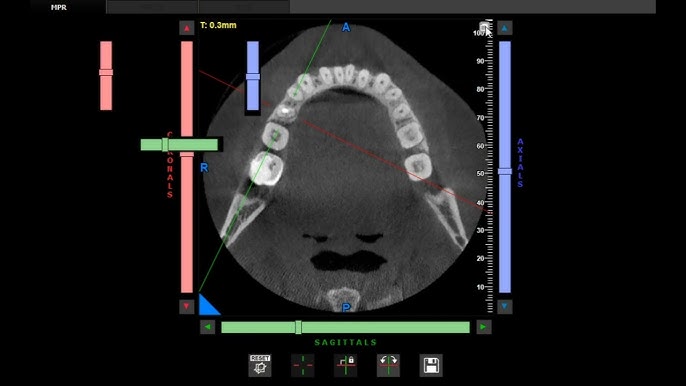

- CBCT (Cone Beam Computed Tomography): A 3D imaging technology that gives detailed information about the root canal anatomy, nerve positions, and surrounding bone structure—often used for complex cases.

Digital X-rays produce highly detailed images that help dentists identify even the smallest infections, hidden canals, or fractures that may not be visible during a clinical examination. The ability to zoom in and manipulate images enhances diagnostic accuracy, ensuring that no detail is overlooked.

With accurate imaging, dentists can plan the root canal procedure more precisely. They can measure canal lengths, locate calcified or curved roots, and determine the extent of infection. This leads to more efficient treatment and a higher success rate.